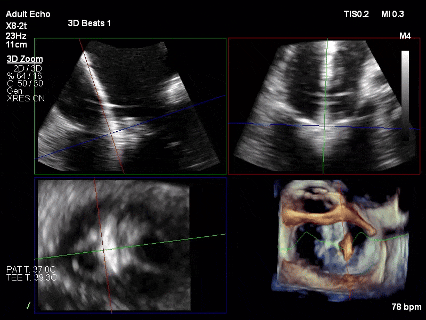

为了避免长时间TEE对食道造成损伤,术前即刻3D-TEE短时进一步明确二尖瓣病变相关解剖情况。

术前Bi-com

术前3D

术前3Dcolor

3D-TEE二尖瓣相关解剖学参数:后叶长度:22-25mm,前叶长度:31-34mm;瓣环AP径:47mm,ML径:48mm;瓣口面积:约7.8cm²;脱垂宽度:30mm,最大连枷间距:14mm。

四条肺静脉均可测及收缩期反向血流

术前即刻TEE进一步明确了二尖瓣反流的机制(DMR)及反流程度(5+),重点完善了病变区域二尖瓣解剖结构的评估,预估手术难点/影响手术效果的解剖结构为冗长的二尖瓣后叶(PML约25mm),宽大的脱垂(Flail Width约30mm),超大的连枷间距(Flail gap约14mm)。